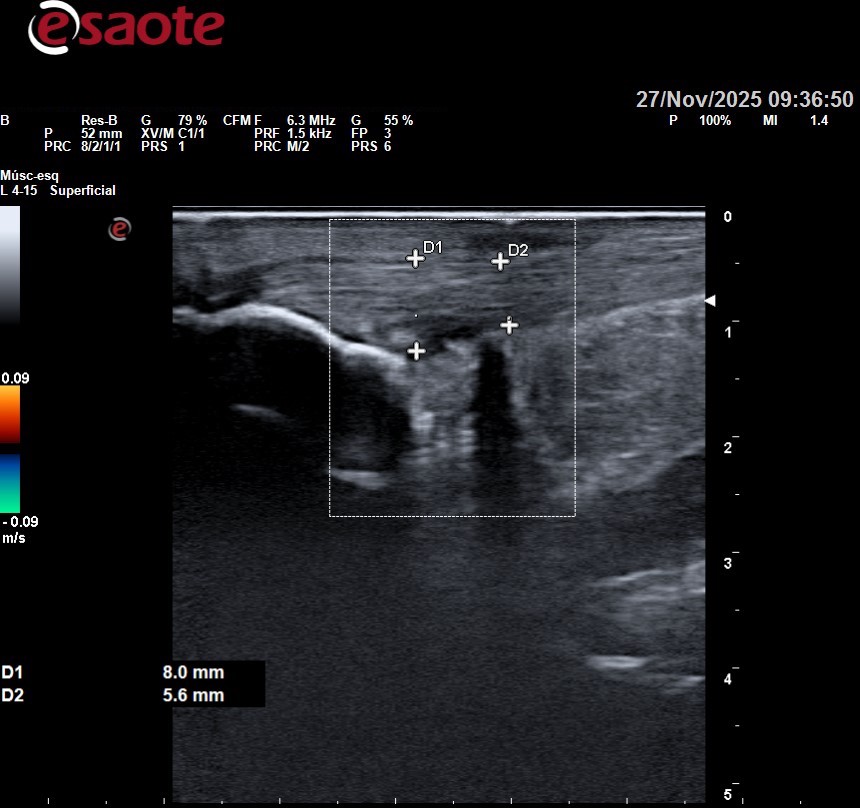

En nuestro caso, utilizamos una técnica muy efectiva para conseguir una amplia reducción del dolor en las tendinopatías de tercio medio: la inyección volumétrica ecoguiada. Esta técnica consiste en la introducción de suero a presión en algunos puntos concretos de la zona problemática con ayuda del ecógrafo.